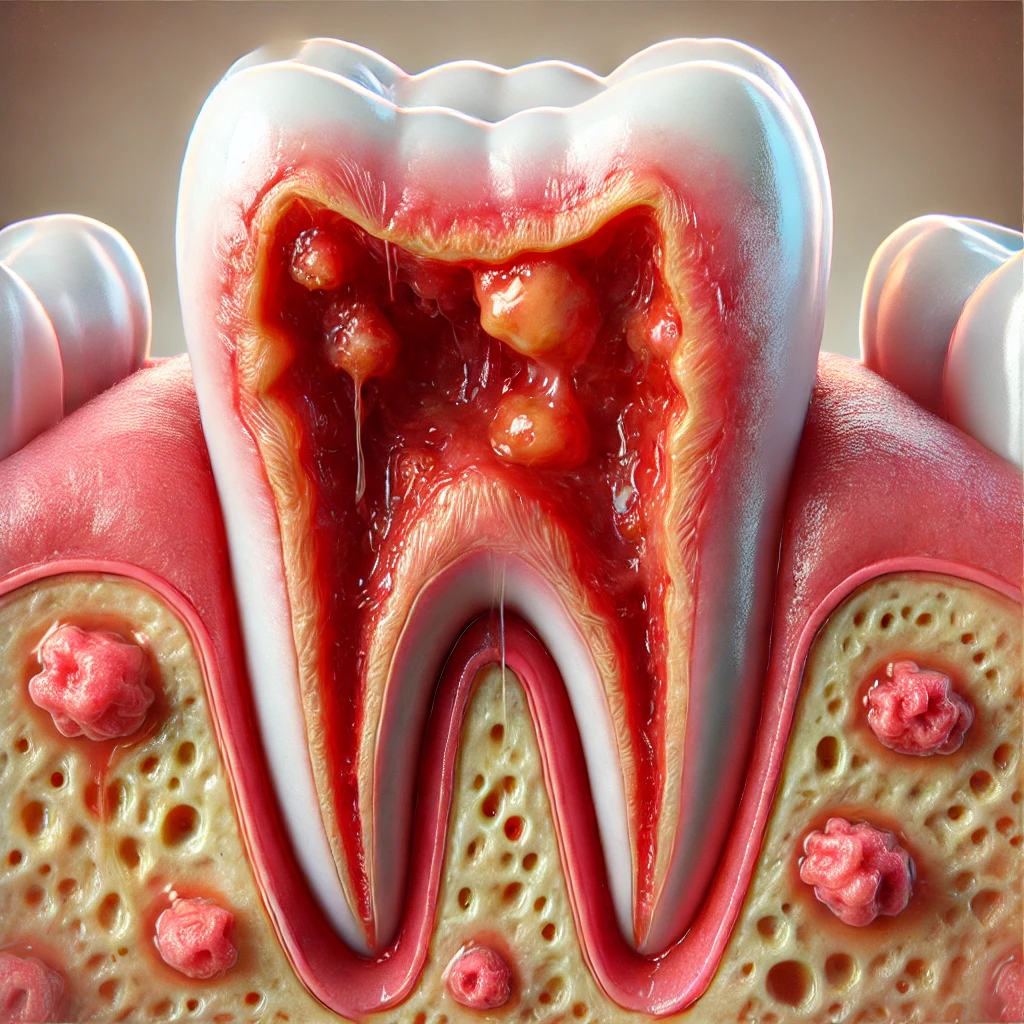

사랑니 발치 후 가장 주의해야 할 합병증은 **드라이소켓(건성발치, Dry Socket)**입니다.

🔹 드라이소켓이란?

발치 부위에서 혈전이 제대로 형성되지 않거나, 형성된 혈전이 빠져나가면서 뼈가 노출되어 심한 통증을 유발하는 상태입니다.

🔹 드라이소켓 증상

✅ 발치 후 3~5일 차에 극심한 통증이 나타남

✅ 진통제를 먹어도 통증이 심하게 지속됨

✅ 발치 부위에서 심한 악취가 나거나 고름이 보임